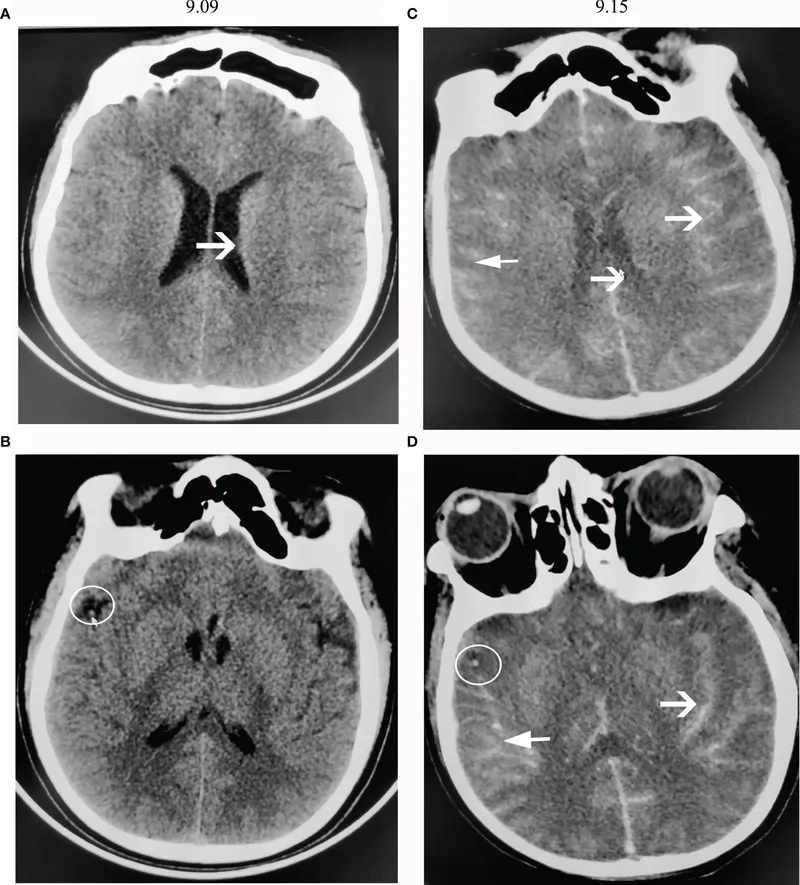

A medical chart of primary amebic meningoencephalitis (PAM)